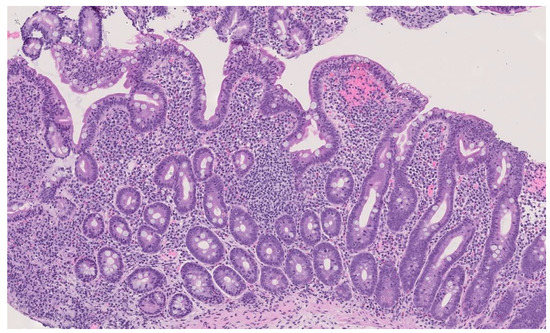

Atrioventricular Block in Celiac Disease: An Unusual Clinical Presentation in a Child. A Case-Based Review

2. Case Presentation